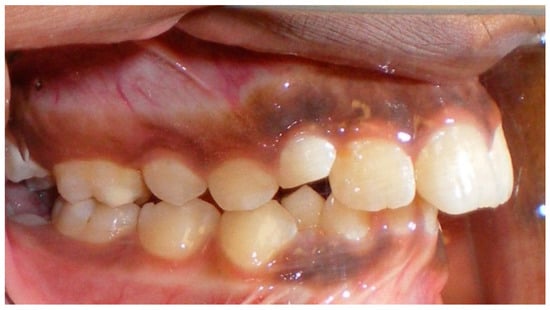

- Assessment of an impacted canine with close proximity to the lateral incisor. Figure 27 shows photographs and a panoramic radiograph of a case in which there is an impacted permanent maxillary right canine in an unfavorable position, a missing mandibular left second premolar and uncoordinated dental midlines. The relationship of the impacted canine to the adjacent lateral incisor cannot be determined from the conventional 2D radiograph. Therefore, CBCT was acquired. Figure 28 shows CBCT images, including coronal, sagittal, axial views, and volume rendering, which demonstrated close proximity of the impacted canine to the lateral incisor, and an area of bone loss buccal to the crown of the impacted canine. Before acquisition of CBCT, the tentative treatment plan was to extract the maxillary right first premolar and bring the canine to the dental arch. However, due to the findings presented by CBCT, the treatment plan was altered in favor of extracting the impacted canine, a clinical decision that was strongly favored by the patient. In this case, the first premolar would substitute for the canine. The maxillary left first premolar and mandibular right first premolar were also extracted. Therefore, each quadrant would have one missing tooth by end of treatment. Orthodontic post-treatment photographs are presented in Figure 29. Figure 30 shows a post-treatment 2D panoramic radiograph. CBCT was neither necessary nor indicated at completion of orthodontic treatment, and therefore only a conventional 2D panoramic radiograph was taken.